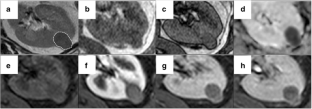

Fig. 4